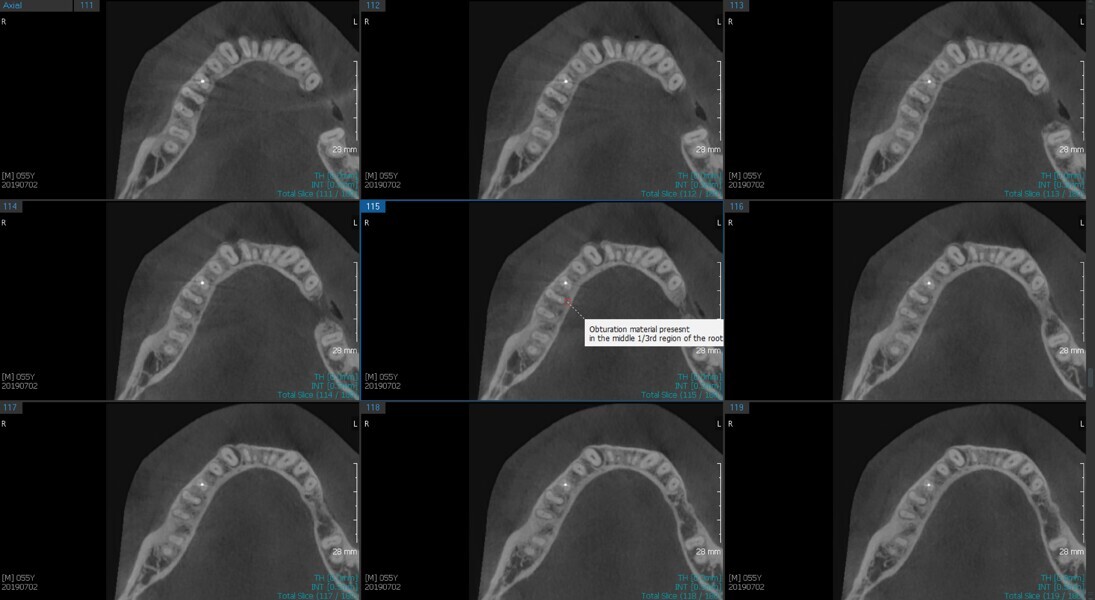

Fig. 6a: Post-op CBCT images of tooth #46 showing adequately obturated canals at all levels to the working length and sealing of the furcation defect.

Fig. 6b: Post-op CBCT images of tooth #46 showing adequately obturated canals at all levels to the working length and sealing of the furcation defect.

Fig. 6c: Post-op CBCT images of tooth #46 showing adequately obturated canals at all levels to the working length and sealing of the furcation defect.

Fig. 6d: Post-op CBCT images of tooth #46 showing adequately obturated canals at all levels to the working length and sealing of the furcation defect.

Fig. 6e: Post-op CBCT images of tooth #46 showing adequately obturated canals at all levels to the working length and sealing of the furcation defect.

Fig. 6f: Post-op CBCT images of tooth #46 showing adequately obturated canals at all levels to the working length and sealing of the furcation defect.

Fig. 6g: Post-op CBCT images of tooth #46 showing adequately obturated canals at all levels to the working length and sealing of the furcation defect.